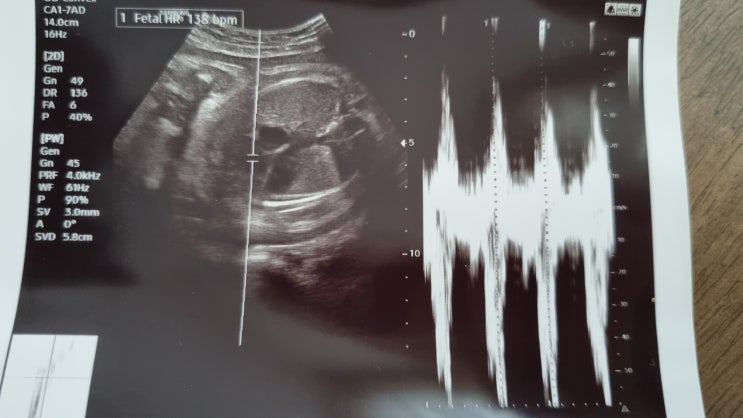

임신 28주 29주 30주 31주 32주 증상 기록 배뭉침 조기진통 자궁경부길이

안녕하세요, 예비 연년생맘 플라입니다! 첫째 때는 막달에 놀이공원도 놀러갈 정도로 컨디션도 최상, 특별...